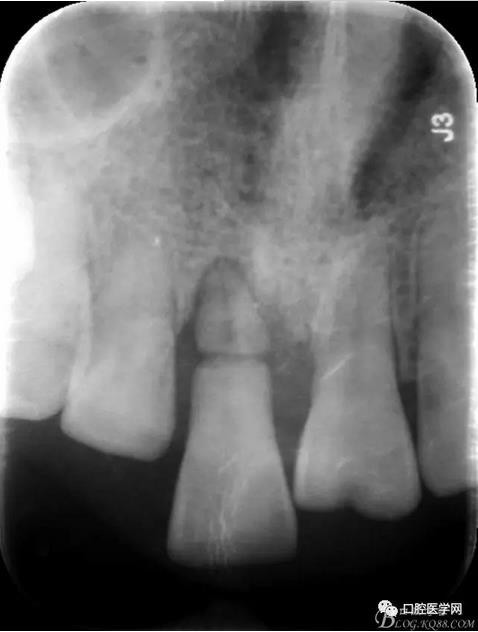

X 光 示:11 根折,根尖無明顯異常

圖1 術(shù)前X光片